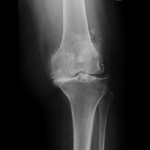

Your doctor will diagnose osteoarthritis based on the medical history, physical examination, and X-rays.

X-rays typically show a narrowing of the joint space in the arthritic knee.